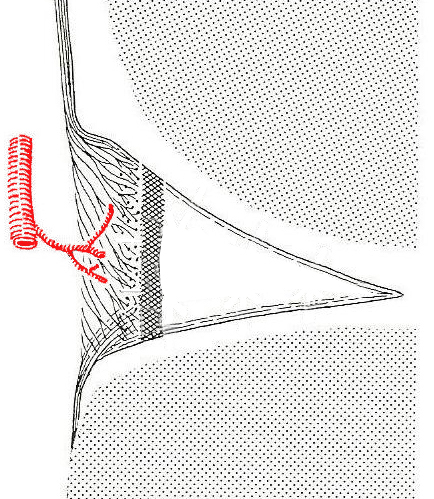

Οι μηνίσκοι αγγειώνονται από την έσω και την έξω αρτηρία του γόνατος, αντίστοιχα, που δημιουργούν ένα θυλακικό αγγειακό πλέγμα, από το οποίο εξορμώνται τα αγγεία που εισέρχονται στο μηνίσκο. Η αγγείωση αφορά στο 30% της περιφέρειας του μηνίσκου (περίπου 50% στα νεογνά, 2-% στους ενήλικες) και αυτό είναι σημαντικό στοιχείο στη θεραπεία της βλάβης του μηνίσκου (εικόνα 3).

Όσον αφορά στην συρραφή του μηνίσκου (εικόνα 5) οι ενδείξεις και τα αποτελέσματα είναι ξεκάθαρα. Απόλυτη ένδειξη και καλύτερα αποτελέσματα έχουν οι περιφερικές ρήξεις που συμβαίνουν στην αγγειούμενη περιοχή του μηνίσκου (τη λεγόμενη “κόκκινη ζώνη”), ενώ σχετική ένδειξη έχουν οι συρραφές στην περιοχή μετάπτωσης αγγειούμενης και μη περιοχής (τη “λευκή ζώνη”).